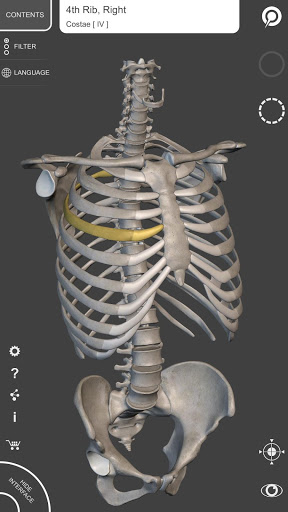

"Skeleton | 3D Atlas of Anatomy" is a next generation anatomy atlas in 3D which gives you availability of interactive highly detailed anatomical models!

Each bone of the human skeleton has been reconstructed in 3D, you can rotate and zoom in on each model and observe it in detail from any angle.

HIGHLY DETAILED ANATOMICAL 3D MODELS

• Skeletal System

• Accurate 3D modeling

• Surfaces of the skeleton with high resolution textures up to 4K

• Rotate and Zoom every model in the 3D space

• Division by regions for a clear and immediate visual of each structure